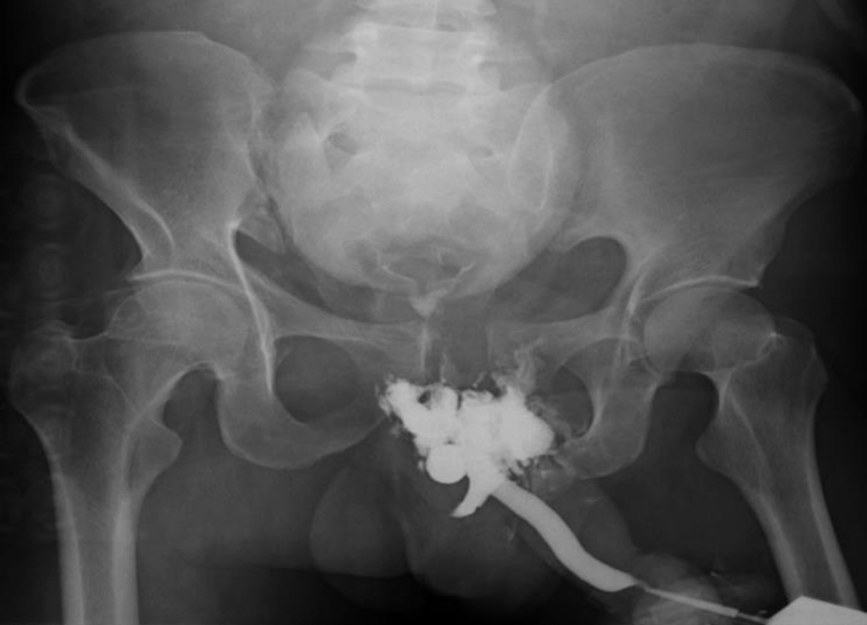

Ανιούσα ουρηθρογραφία (retrograde urethrography, RUG)

Ουρηθρογραφία

Η ανιούσα ουρηθρογραφία (retrograde urethrography, RUG) είναι η καθιερωμένη εξέταση στην πρώιμη αξιολόγηση ενός τραυματισμού της ανδρικής ουρήθρας. Κατά τη διάρκεια της RUG, οποιαδήποτε εξαγγείωση έξω από την ουρήθρα είναι παθογνωμονική για κάκωση της ουρήθρας. Μια τυπική εικόνα για ατελή ρήξη δείχνει εξαγγείωση από την ουρήθρα που συμβαίνει ενώ η ουροδόχος κύστη εξακολουθεί να γεμίζει. Σε μια πλήρη ρήξη παρατηρείται μαζική εξαγγείωση, χωρίς πλήρωση της ουροδόχου κύστης. Αν και η RUG είναι σε θέση να προσδιορίσει αξιόπιστα το σημείο του τραυματισμού, η διάκριση μεταξύ πλήρους και μερικής ρήξης δεν είναι πάντα σαφής. Σε έναν ασταθή ασθενή, η RUG θα πρέπει να αναβάλλεται έως ότου ο ασθενής σταθεροποιηθεί.